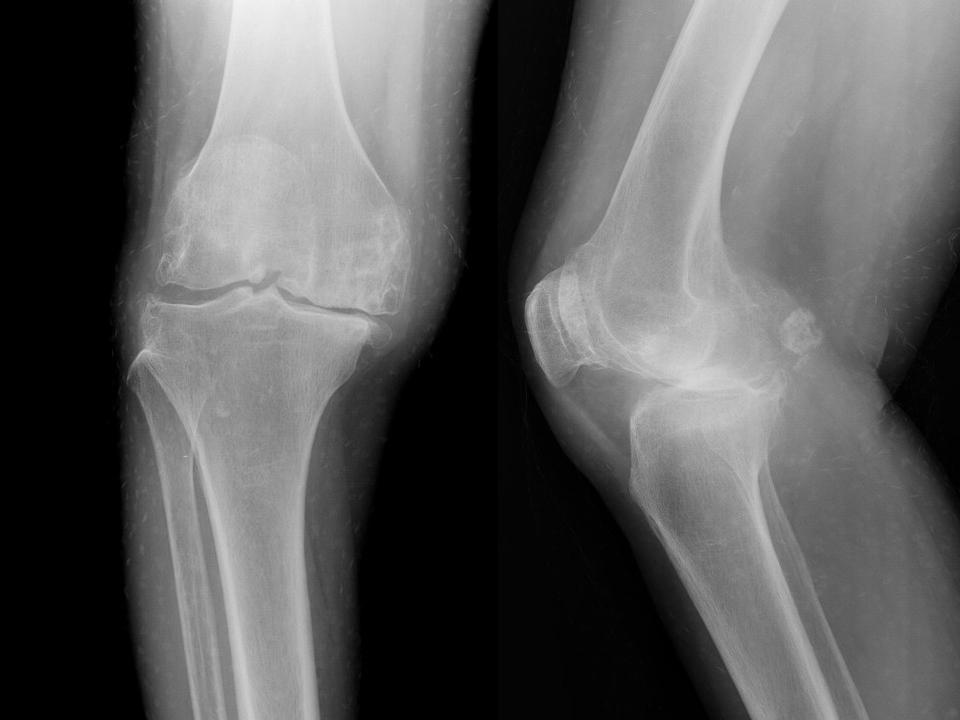

膝关节退行性变 ( 骨赘形成 )